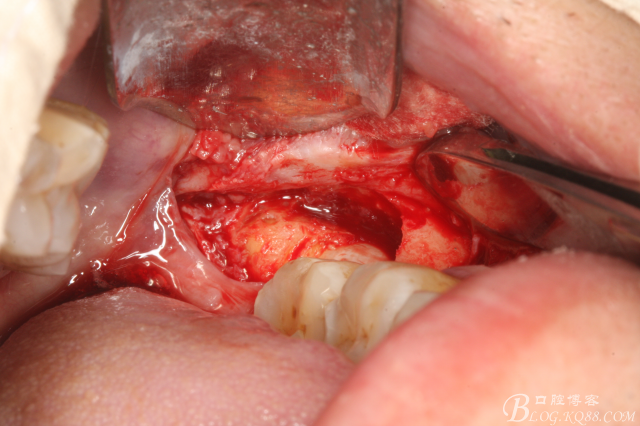

圖2.切開、翻瓣、去骨

圖三、完全暴露38牙根和牙冠